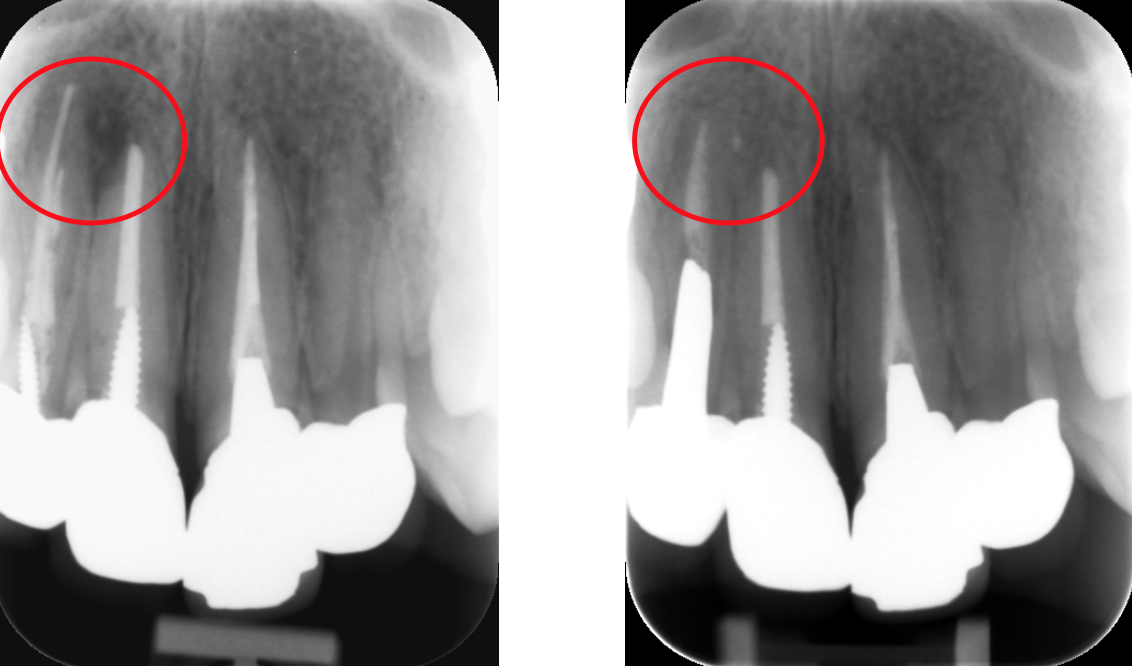

通常の根管治療を行っても症状が良くならない場合には外科的根管治療が必要となってきます。

歯根の外側に感染が及んでいる場合、通常の根管治療では感染源を除去することができないため、感染部位周辺の歯肉から感染源に直接アプローチする必要があります。

感染部周辺の歯肉を切開し、歯根の先端の病変部分を露わにします。

歯槽骨に穴を開け歯の根本から根管治療を行い、感染源を除去します

感染源を除去した後、感染している歯根の先端も取り除きます。

詰物をして歯槽骨の回復を待ち、切開部を縫合して完了です。